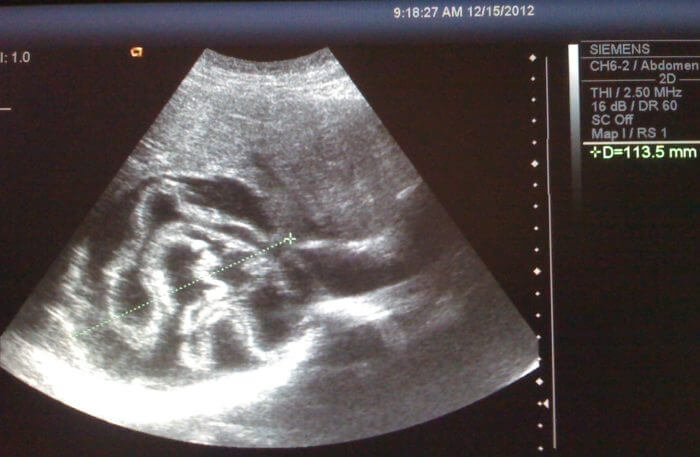

Панченко рассказал, что эхинококкового поражения головного мозга пока не выявили ни у одного заболевшего. Диагноз также не установлен ни у одного из взрослых работников училища, кистозные изменения на УЗИ выявили у одного человека.